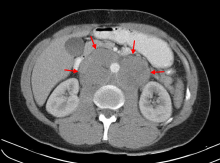

- Mesenteric lymphadenitis after viral systemic infection (particularly in the GALT in the appendix) can commonly present like appendicitis.[13][14]